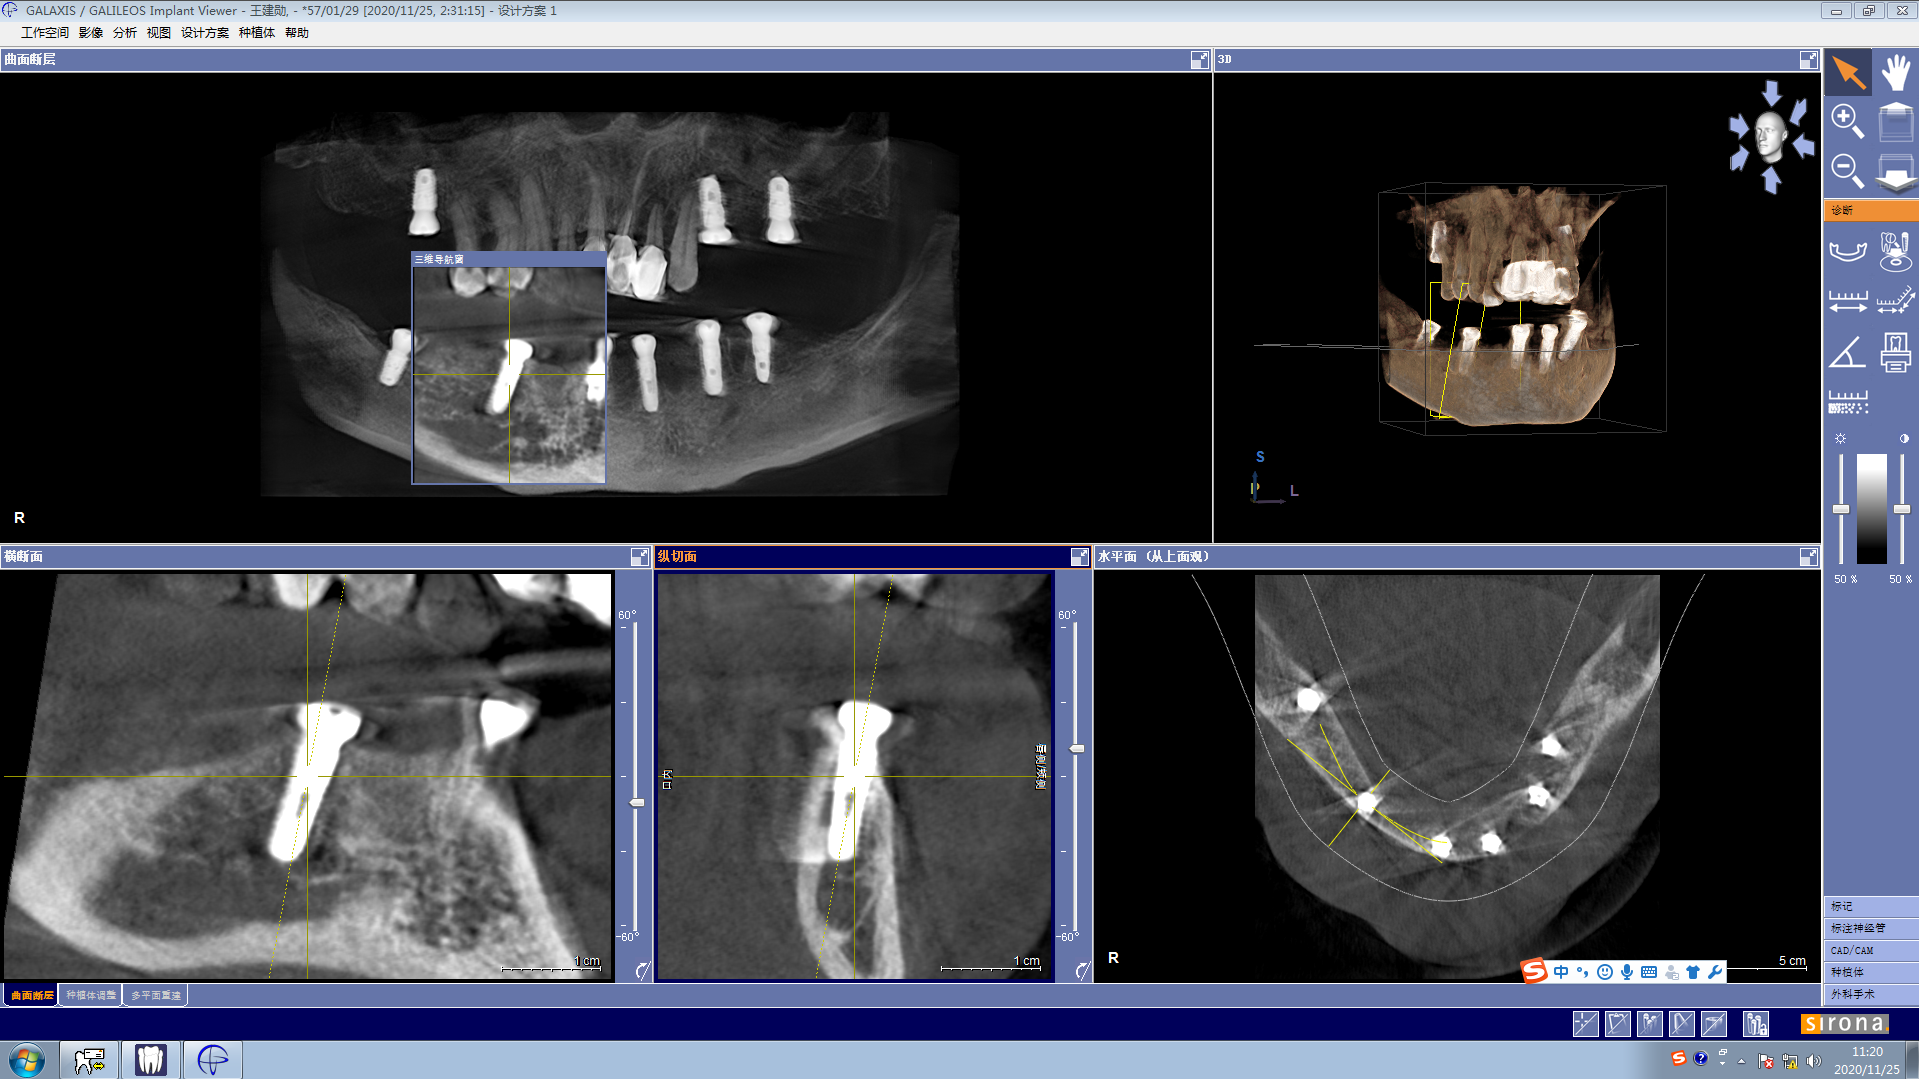

口腔科主要开展牙体牙髓治疗、牙周治疗、牙齿美容、齿槽外科治疗、义齿修复、种植牙、正畸治疗、儿童口腔治疗、口腔粘膜病的中西医结合治疗等多个业务项目。其中特色的种植牙业务及正畸治疗、牙体牙髓治疗项目,都是区内领先。